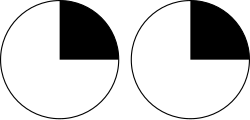

| |

| Visual pathway lesions From top to bottom: 1. Complete loss of vision in the right eye 2. Bitemporal hemianopia 3. Homonymous hemianopia 4. Quadrantanopia 5.& 6. Quadrantanopia with macular sparing | |

The type of field defect can help localize where the lesion is located (see picture given in infobox).